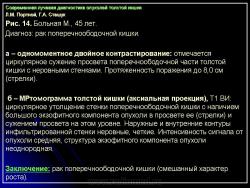

Протокол исследования включал применение импульсных последовательностей (ИП): SE в режиме Т1 с компенсацией дыхания, FSE, STIR (Т2 с синхронизацией дыхания). Основными МРсимптомами опухолевого поражения стенки кишки являются: неравномерное ее утолщение на ограниченном протяжении с соответствующим сужением просвета кишки, наличие внутрипросветного образования с неровными очертаниями и из менением МРсигнала (рис. 14). Толщина пораженной стенки кишки составляла от 7 до 40 мм. Очертания внутренних контуров стенки на уровне поражения были не ровные, бугристые. Интенсивность МРсигнала от из мененной стенки как на Т1, так и на Т2 ВИ была промежуточной (рис. 15), однородность сигнала зависела от преобладания процессов, развивающихся в опухолевой ткани: при имеющихся зонах распада на Т2 ВИ выявлялись очаги повышенной интенсивности МРсигнала. При использовании программы STIR интенсивность сигнала от опухолевой ткани была высокой. Распространение опухолевой инфильтрации за пределы стенки кишки характеризовалось нечеткостью наружных границ опухоли, сетчатым рисунком клетчатки с гетерогенным изменением Мрсигнала, более выраженным на Т1 ВИ (рис. 16б). При прорастании опухоли в смежные органы и структуры не визуализировались границы между измененной стенкой кишки и органом, на который распространялась опухолевая инфильтрация (рис. 17).